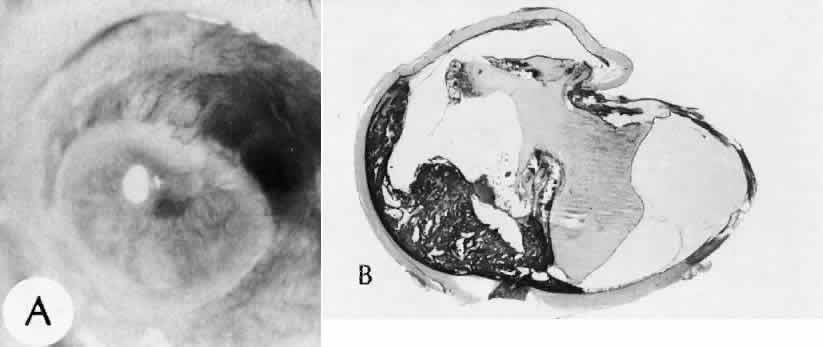

| All ocular surgical procedures are associated with potential complications. A

complication is a deviation from the natural course of the expected

tissue response after a surgical procedure and, in the case of ocular

surgery, usually results in a compromise of ocular function. Complications

may arise from the surgical procedure itself or be the result

of an aberration of the wound healing process. All surgeons will encounter

surgical complications. Eyes afflicted with severe or multiple

disease processes are more likely to develop complications. Early recognition

and a thorough understanding of these deviations from normal allow

for more effective therapeutic intervention.86 Many complications originate from so-called surgical confusion (Fig. 24). Most arise from a lack of knowledge, a lack of judgment, or problems in perception. At times, lack of attention to detail in preoperative planning may lead to a drug reaction, inadequate anesthesia, misplacement of incisions and sutures, or a patient who is unable to control a cough reflex. What is recognized histologically as the immediate cause of the problem may well have its origin in improper planning of the procedure. CATARACT EXTRACTION Intraoperative Complications Complications occurring from the time the patient enters the operating room until the patient leaves the operating room are considered intraoperative.87,88 Misplacement of an anterior segment incision too far anteriorly into the cornea may create an unacceptable degree of scarring or astigmatism, whereas misplacement too far posteriorly (Fig. 25) may cause the incision to enter the ciliary body instead of the anterior chamber, an especially serious event in glaucoma filtering procedures. Misplacement oflimbal sutures (Fig. 26) may cause anterior wound gaping if placed too far posteriorly or posterior wound gaping if placed too far anteriorly. A deep suture may enter the anterior chamber and lead to wicking and a flat anterior chamber postoperatively. A suture placed at different depths in the two sides of the wound results in faulty apposition of the wound edges. Descemet's membrane is only loosely adherent to the posterior stroma and may be stripped into the anterior chamber at the time of the corneal incision placement (Fig. 27) or injection of sodium hyaluronate. Splitting off of Descemet's membrane from the posterior cornea can lead to postoperative intractable corneal edema.89,90 Intraoperative anterior chamber hemorrhage may result from an inadvertent iridodialysis or from the iridectomy wound. The site of hemorrhage is usually found along the scleral side of the cut edge of the wound. This type of hemorrhage rarely leads to serious clinical problems.91 Rupture of the posterior lens capsule (Fig. 28) increases the risk of vitreous loss and limits options for the implantation of an intraocular lens. Retention of lens capsular tissue or vitreous in the wound (Fig. 29) will significantly delay the wound healing process. Vitreous loss leads to an increased incidence of iris prolapse, bullous keratopathy, epithelial downgrowth, stromal overgrowth, wound infection and endophthalmitis, updrawn or misshapen pupil, vitreous bands, postoperative flat anterior chamber, secondary glaucoma, retinal detachment, cystoid macular edema, optic disc edema, vitreousopacities, vitreous hemorrhage, and other sight-threatening consequences.92 Damage to the endothelium during insertion or positioning of the lens was one of the most common problems with intraocular lens implantation until the widespread use of intraoperative viscoelastics. The endothelial cell damage may manifest on the first postoperative day as corneal edema. The course of the edema may wax and wane and ultimately result in pseudophakic bullous keratopathy months or years after surgery. Detachment of Descemet's membrane, inadvertent iridodialysis, cyclodialysis, or rupture of the posterior capsule also may occur during lens insertion and positioning. Expulsive choroidal hemorrhage (Fig. 30) is a rare catastrophic complication often resulting in total loss of the eye.93 The site of hemorrhage is probably a sclerotic choroidal arteriole where the vessel crosses the suprachoroidal space from the scleral canal. The sudden hypotension after surgical penetration of the globe causes a bending and then a rupture of the arteriole.94 Although most hemorrhages are massive and immediate, they occasionally are delayed, and some may not occur for days or weeks after surgery. Delayed choroidal hemorrhage may occur at the time of corneoscleral suture removal,95 because of clinically unapparent wound dehiscence or as a result of perforation of a corneal ulcer. Histologically, massive choroidal hemorrhagic detachment is associated with a retinal detachment. The retina and choroid may herniate through the scleral wound. A ruptured ciliary artery may be found in the suprachoroidal space. Postoperative Complications Postoperative complications may arise from the time the patient leaves the operating room until approximately 6 weeks after surgery.96 A flat anterior chamber is characterized by anterior displacement of the iris to near or in actual contact with the posterior surface of the cornea. The most common cause is leakage of aqueous along one of the suture tracks. Prolonged decompression of the anterior chamber increases the risk of synechiae formation and intractable secondary closed-angle glaucoma. Corneal endothelial damage may result in bullous keratopathy. Choroidal edema (choroidal hydrops or detachment) (Fig. 31) may be associated with a flat anterior chamber and may potentiate the condition. The choroidal edema will slow or stop aqueous production by the ciliary body, further delaying reformation of the anterior chamber. The histologic characteristics of choroidal edema consist of spreading of the choroidal tissue in a fanlike configuration and eosinophilic fluid filling the intervening spaces. The edema fluid may be lost in processing, leaving multiple apparently empty spaces. Iris or lens capsular incarceration into the wound and extending to the conjunctival space (Figs. 32 and 33) may act as a wick through which aqueous can escape, causing a flat anterior chamber. Histologically, iris, which is frequently recognized only by the presence of melanocytes, is seen in the limbal scar, in the limbal episclera, or in both areas. Vitreous wick syndrome consists of vitreous incarceration in the wound, where the vitreous may extend beyond the wound to the subconjunctival space or occasionally to the ocular surface.97 Anchoring of the vitreous anteriorly in this manner may lead to extensive intraocular inflammation even in the absence of infection. The vitreous may act as a conduitfor bacteria, leading to bacterial endophthalmitis.98–100 Pupillary block glaucoma results from isolation of the posterior chamber from the anterior chamber. Occasionally, even in the presence of a clinically patent peripheral iridectomy or iridotomy, the aqueous cannot exit into the anterior chamber. The block results from contact of formed vitreous, lens remnants, or intraocular lens material with the posterior surface of the iris.101,102 The area of contact may include the iridectomy or iridotomy site. Prolonged contact with any of these tissues or materials will cause posterior synechiae formation. After complete posterior synechiae formation, peripheral anterior synechiae develop. Pupillary block glaucoma (closed-angle glaucoma) may not be clinically evident until aqueous production returns to normal levels after surgery. The intraocular lens may be a stimulus for ongoing uveitis, hyphema, and glaucoma (UGH syndrome) (Fig. 34) through multiple factors.103,104 Although lens manufacturing has improved since the early days of fabrication, retained polishing compounds or burrs and irregular surfaces of the lens or loops may cause a low-grade, sterile endophthalmitis.105 Most intraocular lens materials, with the exception of polymethylmethacrylate, have been shown to stimulate some degree of inflammation, which in turn may cause biodegradation of the lens material.106 Several epidemics of lenses contaminated with fungus have been reported. Intermittent movement or continuous pressure of the intraocular lens material against ocular tissue often will result in focal necrosis, tissue disruption, or microhyphema, which may lead to fibrous scarring. This is particularly important when the tissues of the anterior chamber angle are in contact with an anterior chamber lens. Posterior lens loops may erode the iris pigment epithelium and give rise to a type of pigmentary dispersion syndrome (Fig. 35).107,108 Lenses directly supported by the iris have caused lacerations of the iris because of continuous compression by metallic loops (see Fig. 35).109 Iris-supported intraocular lenses are associated with a high incidence of dislocation and subsequent damage to the eye. Corneal endothelial decompensation (Fig. 36) may lead to bullous keratopathy at almost any time in the postoperative period, depending on the state of health of the endothelium at the time of surgery and the extent and nature of injury to the endothelial cells.110,111 Corneal edema may present early in the postoperative period when the cornea has been compromised by advanced Fuchs corneal dystrophy. If the endothelial cells are healthy and the intraoperative trauma is minimal, the signs of decompensation may not appear for decades. Endothelial damage may be the result of mechanical contact with surgical instruments or an intraocular lens, a toxic reaction to solutions used intraoperatively, poor tissue handling techniques, or prolonged and intensive postoperative inflammation.112 Histologically, the corneal epithelium is generally thinned. There may be areas of intraepithelial basement membrane and cyst formation, resulting from malorientation of the squamous epithelial cells during recovery from multiple episodes of bullous separation from Bowman's membrane (Fig. 37). Bullous separation of the epithelial cells varies in extent but is almost always present. Focal areas of interruption of Bowman's membrane and anterior corneal stroma scarring will mark rupture of bullae and subsequent ulceration. In chronic cases, extensive degenerative pannus formation is often seen. The corneal stroma may show a decreased density of keratocyte nuclei. A decrease in or absence of the artifactual clefts of the corneal stromal lamellae suggests edema of the stroma. Descemet's membrane may be focally or diffusely thickened with preexisting Fuchs corneal dystrophy (Fig. 38). In most cases, Descemet's membrane is normal in character and thickness. Often the corneal endothelial density is reduced to the point that only an occasional endothelial cell nucleus can be seen. Infectious bacterial endophthalmitis (Figs. 39 and 40) usually presents early in the postoperative period.113,114 Pseudomonal and streptococcal organisms often cause rapid and total destruction of the eye. Organisms of especially low virulence, such as Staphylococcus epidermidis and Priopionibacterium acnes, may not present for months and may be misinterpreted as sterile endophthalmitis caused by a toxic reaction to intraocular lens materials or phacoanaphylactic endophthalmitis targeted to lens cortical remnants.115–117 Infectious endophthalmitispresenting months after surgery may be caused by a fungal infection or by bacteria of low virulence as pointed out above. Delayed Complications Delayed complications are those that occur more than 6 weeks after surgery. These complications include corneal endothelial decompensation and delayed infectious endophthalmitis, as discussed previously. Elschnig's pearls (Fig. 41) result from aberrant attempts by lens cells attached to the lens capsule to form new lens “fibers.” Histologically, large, clear lens cells (“bladder cells”) are present behind the iris, in the pupillary space, or in both areas. Soemmerring's ring cataract results from the loss of anterior and posterior cortex and nucleus but with retention of equatorial cortex. Apposition of the central portions of the anterior and posterior lens capsule causes a doughnut configuration. Frequently, the doughnut is not complete, so that C- or J-shaped configurations result. Histologically, two balls of trapped and proliferated lens cells are encapsulated behind the iris leaf and connected by adherent anterior and posterior lens capsule in the form of a dumbbell.118 Delayed complications of intraocular lenses themselves are infrequent. The incidence of posterior capsular opacification ranges between 11% and 46% in this period, apparently lower in the presence of an intraocular lens than with extracapsular cataract surgery alone.119,120 Histologically, residual lens epithelial cells are transformed into cells with myofibrillar contractile properties, which wrinkle and opacify the posterior capsule and synthesize the extracellular matrix. Retinal detachment (Fig. 42) occurs in approximately 2% to 8% of intracapsular cataract surgeries, compared with approximately 0.0013% in the general population. The incidence of retinal detachment after extracapsular cataract extraction and posterior chamber lens implantation ranges between 0.6% and 1.5%.121 Vitreous loss increases the incidence of postoperative detachments, particularly if there is vitreous incarceration into the cataract wound. The character of the retinal detachment is independent of the type of cataract surgery or the type of intraocular lens implanted. However, a lower incidence of proliferative vitreoretinopathy appears in cases of extracapsular cataract extraction than was formerly seen with intracapsular cataract extraction. Aphakic or pseudophakic glaucoma122,123 is a nonspecific term referring to a pathologic and sustained increase in pressure after surgery for removal of cataract. In the delayed phase, this glaucoma is mainly caused by secondary chronic angle closure. However, a preexisting predilection to simple open-angle glaucoma may be the cause. Circumferential peripheral anterior synechiae may develop from persistent flat anterior chamber. Focal synechiae are often found adherent to the posterior aspects of the surgical incision. Histologically, the iris is apposed to the posterior cornea, often central to Schwalbe's ring. Posterior synechiae are generally the result of posterior chamber inflammation (caused by iridocyclitis, endophthalmitis, or hyphema) causing iris bomb, and secondary peripheral anterior synechiae (Fig. 43). Histologically, the posterior pupillary portion of the iris is adherent to the anterior face of the vitreous, to the lens remnants, to the intraocular lens, or to all three structures. The anterior peripheral iris is adherent to the posterior cornea (peripheral anterior synechiae), frequently central to Schwalbe's ring. Epithelial downgrowth (ingrowth) (Fig. 44) is one of the most serious causes of pseudophakic glaucoma, in which surface epithelium (probably from the conjunctiva) grows into the anterior chamber. This condition is more likely to occur with fornix-based conjunctival flaps than with limbus-based flaps and in eyes with problems in wound closure, such as vitreous loss, wound incarceration of tissue, delayed reformation of the anterior chamber, or frank rupture of the limbal incision, and when instruments such as iridectomy forceps are contaminated with surface epithelium before they are introduced into the eye. Epithelial downgrowth causes an anterior chamber angle closure by means of peripheral anterior synechiae or lines an open anterior chamber angle and obstructs aqueous outflow mechanically. Histologically, the epithelium is seen to grow most luxuriously and in multiple layers on the iris where there is a good blood supply, but it tends to grow sparsely and in a single layer on the posterior surface of the avascular cornea. The epithelium may extend behind the iris, over the ciliary body, and even far into the interior of the eye. Iris cyst formation (Figs. 45 and 46 is also caused by implantation of surface epithelium onto the iris at the time of surgery or trauma. The cyst generally grows slowly and is accompanied by peripheral anterior synechiae. If extensive, the cysts may cause a secondary chronic closed-angle glaucoma. Histologically, the cyst is lined by stratified squamous or columnar epithelium, sometimes containing mucous cells, and is filled with keratin debris (white or pearly cysts) or mucous fluid (clear cysts). Stromal overgrowth (Fig. 47) is a condition characterized by growth of fibrous connective tissue into the anterior chamber. It is most likely to occur after vitreous loss or tissue incarceration into the surgical wound. The overgrowth may be localized, may be limited to the area of surgical perforation of Descemet's membrane, or may be extensive. When overgrowth is extensive, peripheral anterior synechiae and secondary closed-angle glaucoma result. As with epithelial downgrowth, the stromal overgrowth may extend behind the iris, over the ciliary body, and far into the interior of the eye. Histologically, fibrous tissue generally extends from the corneal stroma or is in continuity with it, through a large gap in Descemet's membrane. The fibrous tissue often covers the posterior cornea, fills part of the anterior chamber, occludes the anterior chamber angle, and may extend into the vitreous compartment to attach posteriorly onto the retina. Bacterial inflammation is rare in the delayed period after surgery, except after filtering procedures in which bacteria can gain access to the inside of the eye by way of the bleb (Fig. 48). Another exception to this rule is Priopionibacterium acnes or Staphylococcus epidermidis endophthalmitis, which infects lens remnants and may not clinically manifest for many months after cataract extraction. Fungal endophthalmitis (Fig. 49) may take the form of keratitis or endophthalmitis. Histologic characteristics of end-stage endophthalmitis include fibrovascular organization centered about a chronic nongranulomatous inflammatory reaction contiguous with lens remnants, causing cyclitic membrane formation and retinal detachment. Multiple small foreign bodies, inadvertently introduced at the time of surgery, can cause a delayed chronic nongranulomatous or granulomatous inflammatory reaction. Phacoanaphylactic endophthalmitis or sympathetic uveitis may occur after extracapsular cataract extraction (discussed elsewhere in these volumes). Healed cataract wounds may rupture because of trauma. In particular, blunt trauma to the eye may cause ocular rupture, often at the site of a cataract scar that remains weaker than surrounding tissue. Cystoid macular edema, or Irvine-Gass syndrome, is an inflammatory, degenerative condition of unknown cause that involves primarily the macula and leads to temporary or permanent loss of macular function. This condition can occur anytime after cataract surgery (even up to 5 years), but most cases occur within 2 months of surgery. The initial clinical sign is a sudden decrease in visual acuity. At least 50% of the cases are self-limiting, and the macular edema resolves completely, with or with-out therapy, within 1 year. Most patients experi-ence spontaneous recovery of vision. In a few cases,however, the intraretinal edema may persist, andsecondary permanent complications, such as lamel-lar macular hole formation, may occur. The condi-tion can be precipitated or aggravated by topicalepinephrine therapy for glaucoma. The cause ofcystoid macular edema is unknown, but in somecases (probably the minority), vitreous traction or aposterior vitritis may play a role (Fig. 50). Histo-logically, iritis, cyclitis, retinal phlebitis, and retinal periphlebitis have been noted. Whether these conditions cause the cystoid macular changes or are simply incidental findings in enucleated eyes is not clear. A lamellar macular hole may occur as a permanent complication. Ophthalmoscopically (best seen with a slit-lamp biomicroscope), multiple (usually four or five) intraretinal microcysts are seen in the macular area, obscuring the normal foveal reflex. The cysts fill early with fluorescein, and pooling causes a characteristic stellate geometric pattern that persists for 30 minutes or longer. Granular fluid is seen in the microcystic spaces (Fig. 51). The anatomic basis of early cystoid macular edema probably is edema of Müller cells; later, Müller cell membranes break down and the edema becomes extracellular. PENETRATING KERATOPLASTY Immediate Complications Complications of penetrating keratoplasty may arise in the selection of donor material. The success of a graft depends on the health and integrity of the donor endothelium. Compromise of endothelial function attributable to the age of the donor, preexisting endothelial disease (Fuchs corneal dystrophy), toxicity of storage procedures, microbial infection, or intraoperative trauma will lead to early endothelial decompensation. Immunologic testing and a careful history of infectious disease of the donor (AIDS, hepatitis, Jakob-Creutzfeldt disease, and rabies) are essential because the virus may be harbored in the donor tissue. Retention of significant amounts of host Desce-met's membrane and presence of nonviable peripheral host tissue in patients with alkali burns are additional potential intraoperative problems. Improper apposition of the donor-host interface may lead to multiple structural and refractive problems. Overriding of the wound edge is a likely site for wound leak, leading to a flat anterior chamber, which in turn may lead to central anterior synechiae to the wound or total anterior synechiae. Malposition of the posterior wound edge is likely to enhance fibrous tissue proliferation, which may remain in the local region of wound or may spread peripherally or even centrally (stromal in growth). Postoperative Complications Penetrating keratoplasty has the same risks for microbial infection, epithelial ingrowth, stromal ingrowth, and expulsive choroidal hemorrhage, as does anterior segment surgery in general. Immune rejection of a corneal graft is an unusual complication, except when the host tissue is extensively vascularized. Immune stromal graft rejection clinically manifests 2 to 3 weeks postoperatively and is heralded by inflammatory signs associated with progressive vascularization of the graft. Histologically, a central necrotic area is bounded peripherally by a zonal inflammatory response. Polymorpho-nuclear leukocytes predominate near the necrotictissue, surrounded by a zone of lymphocytes and plasma cells. The endothelial layer may undergo specific graft rejection. This is recognized clinically as a centrally advancing, linear, posterior corneal opacity (Khoudadoust's line). Histologically, there is a chronic nongranulomatous inflammatory reaction about necrotic endothelial cells. Delayed Complications Graft failure is a nonspecific term used to indicate progressive or persistent opacification of a donor cornea. In most cases, the histologic characteristics are those of corneal endothelial decompensation. In some cases, particularly those with underlying systemic disease or ocular surface abnormalities, there may be extensive corneal ulceration or perforation. REFRACTIVE SURGERY Immediate Complications Accidental perforation of the globe is possible with any of the refractive procedures. Variability of the incision depth is one of the most important factors in the ultimate variability of the refractive correction obtained by the procedure. Postoperative Complications Microbial endophthalmitis, even leading to blindness, has been reported as a complication of this type of procedure. There appears to be an acute postoperative endothelial cell loss that is not progressive. Wound healing of radial keratoplasty has been complicated by intrastromal epithelial cyst formation and a generalized decrease in the rate of healing of the incision (Fig. 52). Complete healing and refractive stability may not be realized for years. Epikeratophakia procedures have been complicated by delayed reepithelialization of the grafted tissue and epithelial retention or proliferation along the interface between the lenticule and the host tissue. Persistent folding of Bowman's membrane underlying the grafted tissue and abnormal keratocytes in the underlying recipient stroma may lead to a poor visual result. In some cases, the lenticule of keratomileusis has been slow to be repopulated by host keratocytes, which may be responsible for persistent opacification of the grafted area. Thickening of the epithelial basement membrane, a decreased density in hemidesmosomes, and abnormalities of Bowman's membrane have been observed. Abnormal proteoglycan synthesis also has been suspected in these cases. Visually significant opacities at the tissue-synthetic material interface have been noted with corneal intrastromal inlay procedures (Fig. 53). This material, which has been found to contain lipid, appears to accumulate over time. Corneal inlays of all types have been complicated by necrosis of the tissue overlying the pocket and extrusion of the synthetic material. Delayed Complications An early type of radial keratotomy, which included incisions of the internal surface of the cornea, has resulted in a high degree of corneal endothelial decompensation 20 years after the procedure, regardless of the age of the patient at the time of surgery. LASIK Complications of LASIK Variability in actual flap thickness has also been noted in several studies. The lack of uniformity of flap dimensions may be important in repositioning the flap in the stromal bed.124 Microfolding of the anterior corneal flap was found in 94% of eyes examined by confocal microscopy. The folding was attributed to stretching of the tissue during laminectomy or to imprecise registering of the flap tissue with the lamellar bed.75 The character of the blade edge, particularly of a blade that has been used for more than one procedure, also influences the morphology of the stromal incision. Notching of the blade profile with repeated use has been observed by scanning electron microscopy. Notching of the blade edge also appears to be associated with accumulation of tissue remnants on the surface of the blade.67,68 The tissue remnants can be identified as reflective interface particles by confocal microscopy. Potential sources of the material include metal from the microkeratome blade, cotton, lipid, inflammatory cells, intact epithelial cells, or remnants.75 Complications occur in approximately 3% to 5% of LASIK procedures.78,125,126 Intraoperative compilations are primarily related to creation of the lamellar flap. Included among this type of complication are flap irregularities, epithelium and other material within the lamellar interface, regular and irregular astigmatism, flap loss, displacement, and button-holing. Infection is a rare but potentially serious complication.78,127–131 Perforations of the globe have been described.132–137 Potential complications at 6 months include epithelial ingrowth, corneal flap melting, decentered ablation, and irregular astigmatism with loss of best-corrected visual acuity.124 Complications related to abnormal endothelial cell function have been infrequent.134,138–140 Progressive epithelial ingrowth may occur characterized as a continuous sheet of epithelium contiguous with the flap edge (Fig. 54).124,141 Epithelial ingrowth into the intrastromal interface may be associated with enzymatic digestion of the cornea.142 Diffuse interface keratitis is a condition char-acterized by acquired opacification at the level ofthe intralamellar bed after a LASIK procedure(Fig. 55).143 Many causes of the syndrome have been reported144–147 and include exotoxins released from sterilizer reservoir biofilm148 and debris on the microkeratome blade149 and methylcellulose sponge material.150 Most cases resolve spontaneously.151 The resistance of eyes to trauma after LASIK, even in the absence of healing appears to be similar to unoperated human eyes as evaluated in a model of postmortem refractive procedures performed on autopsy eyes.152 In this model, radial keratotomy incisions predisposed rupture at lower energy levels than in unoperated eyes.153 Postoperatively, there was a decrease in intraocular pressure measured by central tonometry that was statistically significant. Differences in pneumotonometry were less substantial, with greater reliability of pneumotonometry than Goldmann applanation tonometry after LASIK.154 GLAUCOMA SURGERY Immediate Complications Creation of a button hole in the conjunctiva is not serious in cataract surgery but may lead to failure in filtering procedures. Misplacement of the incision too far posteriorly may cause the incision to enter the ciliary body instead of the anterior chamber, an especially serious event in glaucoma filtering procedures. Postoperative Complications Cataract formation may be caused or accelerated by glaucoma surgery, even if the lens is not apparently damaged by physical contact. The cataract may be a result of shunting of the aqueous through the iridectomy, so that the anterior and posterior surfaces of the lens are not properly nourished. Bacterial endophthalmitis may occur. Hypotony and choroidal detachment have complicated trabeculectomy procedures more common with full-thickness filtering procedures. Seton devices have been complicated by conjunctival erosion by the synthetic parts, blockage of the proximal orifice, corneal decompensation, extrascleral tube compression, and blockage of the distal orifice. Delayed Complications Procedures to lower intraocular pressure function by transconjunctival filtration, absorption of aqueous into the subconjunctival vessels, recanalization, reopening of drainage channels, passage through areas of perivascular degeneration, or any combination. Incorrect placement of the incision, hemorrhage, inflammation, prolapse of the intraocular tissue into the filtration site, dense fibrosis, peripheral anterior synechiae formation and secondary chronic closed-angle glaucoma, and endothelialization of the bleb may cause filtration failure. The histology depends on the underlying cause. Even in the delayed period, bacteria may gain access to the interior of the eye, by way of the bleb, and cause endophthalmitis. RETINAL REATTACHMENT SURGERY Intraoperative Complications A misplaced implant, explant, or scleral suture can lead to an improper scleral buckle or premature drainage of the subretinal fluid. Misplaced, insufficient, or excessive diathermy or cryotherapy can cause unsatisfactory results by not closing the retinal hole. Cut or obstructed vortex veins can lead to choroidal detachment or hemorrhage (Fig. 56), which is most often caused by hypotension induced by surgical drainage of subretinal fluid. Overuse of scleral cryotherapy or diathermy also may be a cause. Other causes include cutting or obstruction of vortex veins and incision of the choroidal vessels at the time of surgical drainage of the subretinal fluid. Retina may be incarcerated in a surgical drainage site. Acute closed-angle glaucoma may be the result of the buckling procedure, especially if unaccompanied by drainage of the subretinal fluid or anterior chamber paracentesis. If the glaucoma is not recognized, central retinal artery occlusion may occur and result in blindness. Postoperative Complications The original retinal hole may remain open, or a new one may develop or be missed preoperatively. Choroidal detachment and choroidal hemorrhage also may occur during this time. Acute or subacute scleral necrosis (Fig. 57) may follow retinal detachment surgery after days or weeks and is probably caused by ischemia rather than infection. In the acute form, the clinical picture generally starts a few days after surgery and may resemble a true infectious scleritis but without pain. There is a sudden onset of congestion, edema, and a dark red or purple appearance of the tissues over the implant or explant. Discharge is not marked or is absent altogether. The vitreous over the buckle generally becomes hazy but may be clear. The cornea remains clear but the involved area of the sclera becomes completely necrotic. In the subacute form, the clinical picture starts with pain approximately 2 to 3 weeks after surgery. The globe may be congested but no discharge occurs. The vitreous over the buckle may be hazy or clear. The sclera in the region of the buckle is necrotic. Infection in the form of scleral abscess, endophthalmitis, or keratitis may be secondary to bacteria or fungi and is characterized by redness of the globe, discharge, and pain (Fig. 58). Anterior segment necrosis (Fig. 59) is thought to be secondary to interruption of the blood supply to the iris and ciliary body, usually by temporary removal of one or more rectus muscles during surgery. Encircling elements, lamellar dissection implants, explants, and cryotherapy or diathermy may also cause compromised blood supply. Clinically, keratopathy and intraocular inflammation usually develop in the first postoperative week. Corneal changes consist of striate keratopathy and corneal edema with epithelial bullae. Chemosis, anterior chamber flare and cells, large keratic precipitates, and white deposits on the necrotic lens capsule characerize intraocular inflammation clinically. The clinical findings are often mistaken for an infectious endophthalmitis. Later, the pupil becomes dilated. Shrinkage of the iris toward the side of the greatest necrosis and hypoxia results in an irregular pupil. Cataract, hypotension, ectropion uveae, and finally phthisis bulbi develop. A high incidence of anterior segment ischemic syndrome is seen after scleral buckling procedures in patients with hemoglobin sickle cell disease. In hemoglobin sickle cell disease, the increased frequency of anterior segment necrosis is most likely related to the increased blood viscosity and tendency toward erythrocyte packing that is found in these patients, especially those with a decreased oxygen tension. Histologically, ischemic necrosis of the iris, ciliary body, and lens epithelial cells is present, frequently only on the side of the surgical procedure. Hemorrhage in the postoperative period may be caused by a delayed expulsive choroidal hemorrhage that most probably results from necrosis of a blood vessel induced by the original diathermy or cryotherapy or to erosion of an implant or explant. Acute closed-angle glaucoma probably occurs after a retinal detachment procedure in which an encircling element or a high buckle is created. Acute closed-angle glaucoma occurs in approximately 4% of scleral buckling procedures. The pathogenesis of the angle closure is not known, although pupillary block or swelling of the ciliary body is a proposed mechanism. The buckle decreases the volume of the vitreous compartment, displacing the vitreous and lens-iris diaphragm anteriorly. Corneal edema on the first postoperative day, especially if accompanied by ocular pain, should be considered glaucomatous until proved otherwise. Histologically, the anterior displacement of intraocular structures results in encroachment of the iris on the anterior chamber angle and resultant closed-angle glaucoma. Chronic simple glaucoma may become apparent when the hypotension of a retinal detachment is alleviated by surgery. Delayed Complications Vitreous retraction by itself is of little importance, but when it is associated with fibrous or glial membranous proliferation on the internal or external surface of the retina, it can cause retinal detachment with or without retinal hole formation. Prolifera-tive vitreoretinopathy is extensive cellular prolif-eration (glial cells, retinal pigment epithelial cells,fibroblasts, and Müller cells) on retinal tissue asso-ciated with a total retinal detachment. The mem-branes distort the surface of the retina to cause a cel-lophane appearance and extend to form star foldsand other configurations of fixed retinal folds. His-tologically, fibroglial membranes can be seen onthe internal or external surface of the retina. With contraction of the myofibroblasts of the membranes, the architecture of the retina will be markedly distorted.155 An implant or explant may migrate externally along the surface of the globe and through the conjunctiva or internally into the globe (Fig. 60). Internal migration may cause hemorrhage, retinal detachment, or infection. In this setting, the conjunctival epithelium may gain access to the interior of the eye. The resultant conjunctival epithelial ingrowth complicates an already compromised eye. Retinal tacks also may migrate as far as the anterior chamber. A retinal hole may develop de novo or secondary to obvious vitreous pathology. Other late problems include heterophoria, disturbances of lid position, and secondary glaucoma (hemolytic, closed angle from prolonged or recurrent inflammation, or neovascular associated with retinal ischemia). Macular degeneration and puckering may occur if cryotherapy or diathermy has been used. |